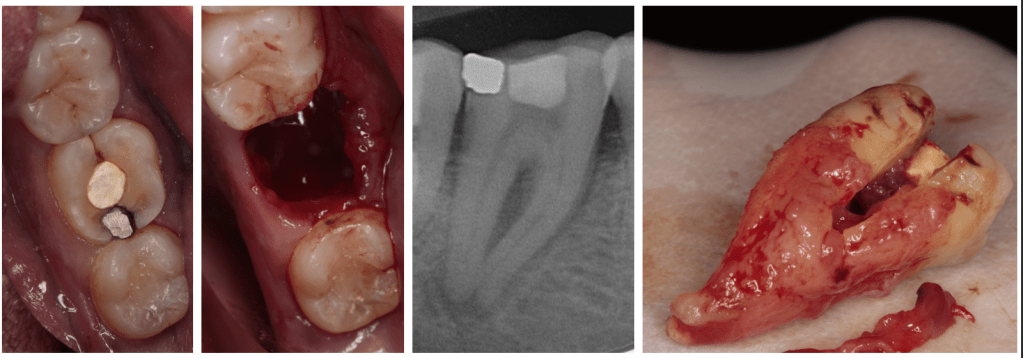

Diente fisurado, no tratable